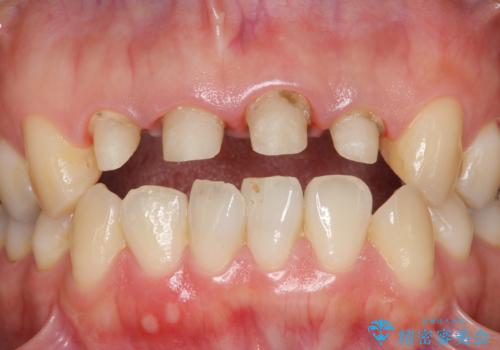

- 歯ぐきの黒っぽさ、暗い色調の前歯の改善を求めて来院されました。

金属を用いたコア・クラウンが装着されており、全ての金属を除去したのちのメタルフリー治療を計画します。

ファイバーコア・セラミッククラウンは金属を用いない審美的な治療法です。